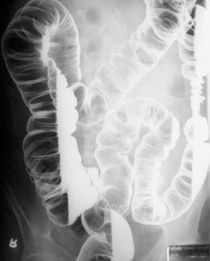

바륨 대장 조영술 바륨 대장 조영술 이미지

• 이중바륨 대장 조영술

항문을 통해 작은 튜브를 삽입하고 바륨 조영제를 넣고 대장 내부를 공기로 확장시킨 다음, 대장 속의 대장 점막에 이상이 있는지 검사하는 방법이다. 검사 중 진통제나 수면유도제가 필요치 않으며 전체 대장을 안전하게 검사할 수 있다는 장점이 있는 반면, 정확한 검사를 위해 하제를 이용하여 장을 비우는 것이 필요하고 방사선 노출 위험이 있다는 단점이 있다. 무엇보다 용종에 대해서 예민도가 대장 내시경 검사에 비해 낮아 작은 용종이나 암을 발견하지 못할 수 있다. 용종이나 암이 의심되는 경우 정확한 진단 및 조직검사를 위해 대장 내시경 검사를 추가로 받아야 한다.